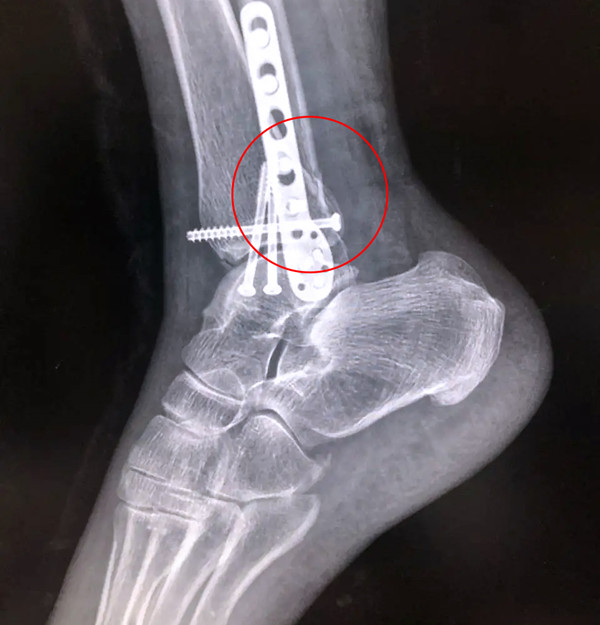

有一种特殊类型的踝关节骨折,可能在X影像平片上就不能显示出来,它就是胫骨的关节面往里塌陷,我们又称之为叫“Pilon骨折”。当它往里塌陷后,我们在X影像平片上可能看不出来它是否塌陷,但是我们在CT上可以360°看到踝关节的影像,这样就可以看出患者是否存在踝关节塌陷的骨折。同样道理,我们在做Pilon骨折手术的时候,普通二维的X影像并不能判断我们手术复位情况的好坏,这个时候如果医生手上有能够照三维影像的工具,那么对于医生的准确手术是非常有好处的。

三维影像 助力复杂手术准确治疗